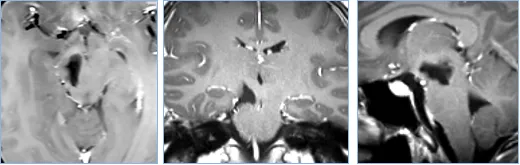

30岁女士,有复视和轻微右侧偏瘫,a、b图患者术前MRI显示中脑肿瘤,患者最初接受立体定向囊肿抽吸和间质放疗,并被诊断为毛细胞型星形细胞瘤,但肿瘤仍在生长。

巴教授为其手术,无手术并发症,f图显示伤口愈合正常,患者预后良好,无神经功能缺损。组织病理学检查为1级毛细胞型星形细胞瘤。g、h图术后MRI影像显示,肿瘤全切。随访MRI记录手术后9年无肿瘤复发。